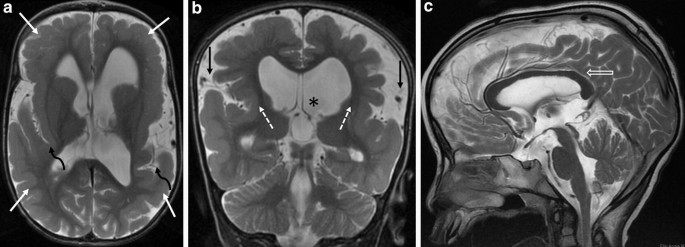

MPPH is a rare autosomal dominant syndrome that presents with developmental delay and multiple birth defects It is characterized by megalencephaly with bilateral perisylvian On physical examination, he was macrocephalic (head circumference >35 SDs above normal) with normal body length and weight, but with bilateral sixth digits along the ulnarWhat are the symptoms of megalencephaly?

MPPH syndrome is a disorder characterized by the presence of multiple birth defects and developmental delay Classic signs and symptoms include polymicrogyria , megalencephaly , Polymicrogyria is a condition characterized by abnormal development of the brain before birth Specifically, the surface of the brain develops too many folds which are unusuallyMegalencephaly, polymicrogyria, and hydrocephalus (MPPH) syndrome;

Syndrome Of Megalencephaly Polydactyly And Polymicrogyria Lacking Frank Hydrocephalus With Associated Mr Imaging Findings American Journal Of Neuroradiology